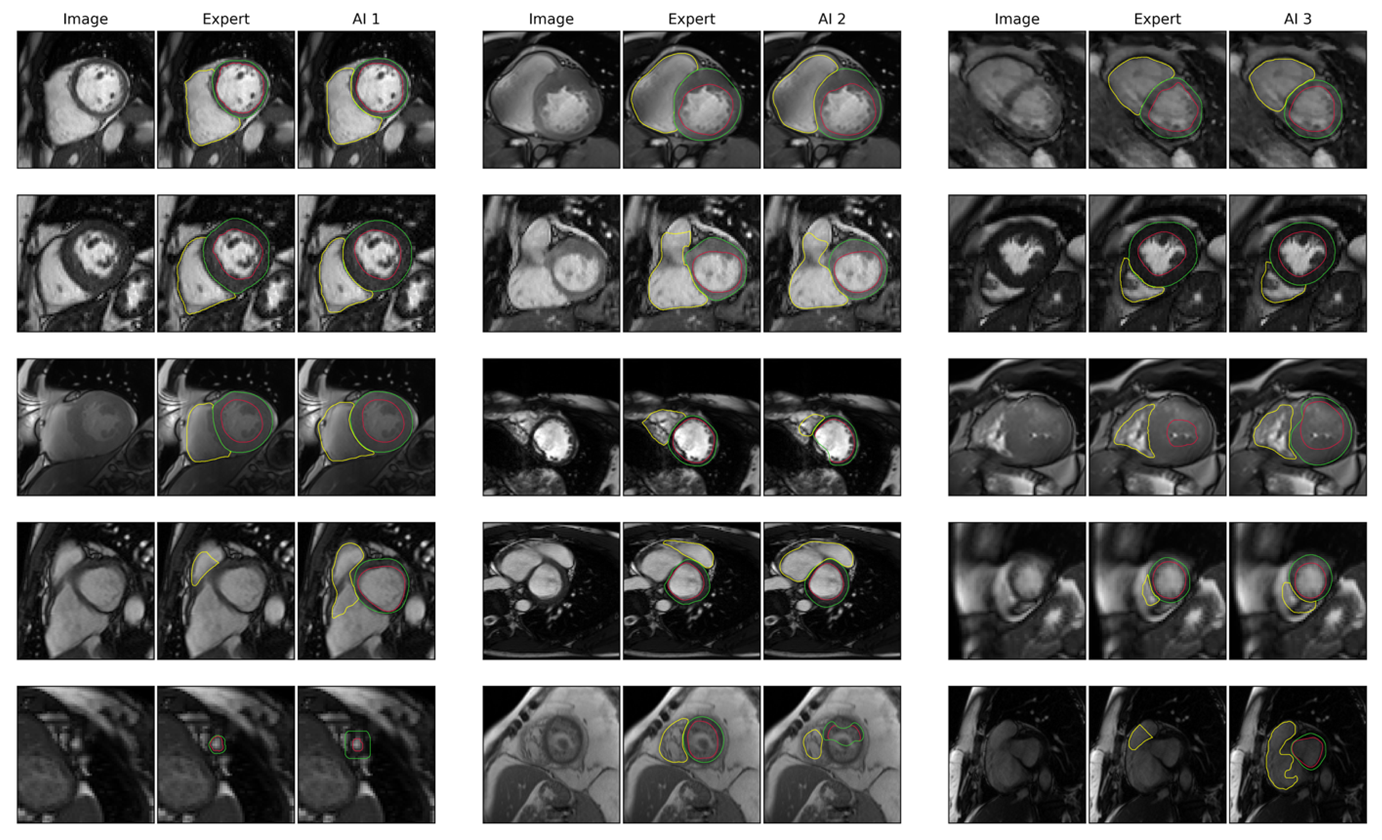

Figure 2: Segmentation Examples Caption: Each three-column subsection shows the base image (first column), the expert and the AI segmentations (columns 2 & 3). Example images show excellent segmentations in the first two rows. But they also include difficult cases, such as artefacts (section 1, row 3), a large apical thrombus (section 2, row 5) and a hypertrophic heart in end-systole (section 3, row 3).

Figure 2: Segmentation Examples Caption: Each three-column subsection shows the base image (first column), the expert and the AI segmentations (columns 2 & 3). Example images show excellent segmentations in the first two rows. But they also include difficult cases, such as artefacts (section 1, row 3), a large apical thrombus (section 2, row 5) and a hypertrophic heart in end-systole (section 3, row 3).